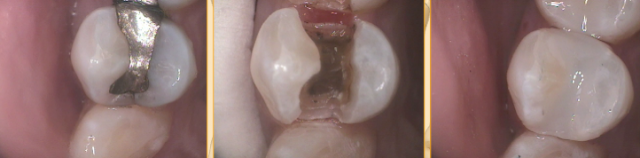

I have a few different composites in my office depending on the location, size, and expectations of outcome on the tooth. I use Sonicfill when there isn’t a lot of discoloration on the tooth, because it’s too translucent to mask amalgam staining well. I use Estelite Omega in some cases and Venus Diamond in others. I always layer when I’m not using a bulk composite — and even when using a bulk composite, I find that you have to condense repeatedly to avoid air bubbles.